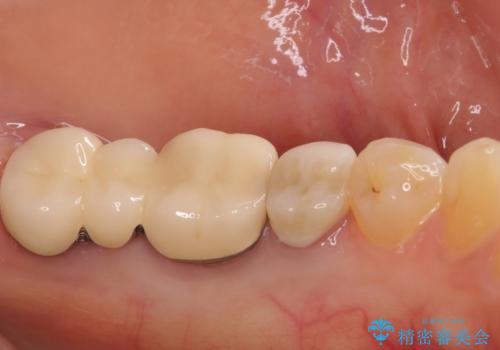

- 抜歯が必要と診断された奥歯の治療を希望して来院された患者様です。

一番奥の歯は歯根の一部を残した状態で、手前の歯とブリッジが装着されていました。

奥歯は歯根周辺の歯槽骨が広範囲に失われており、抜歯が必要と判断されました。

ブリッジの手前側の歯は、根管治療が必要な状態でした。

手前は根管治療後に補綴治療を、奥は骨造成後にインプラント埋入し、手前の歯と同時に補綴治療を行うこととしました。

根管治療と合わせて、穴の開けられている部分を修復したところ、炎症による歯槽骨吸収に改善が見られました。

歯槽骨の高さや幅を回復することができ、望ましい位置にインプラントを埋入することができました。